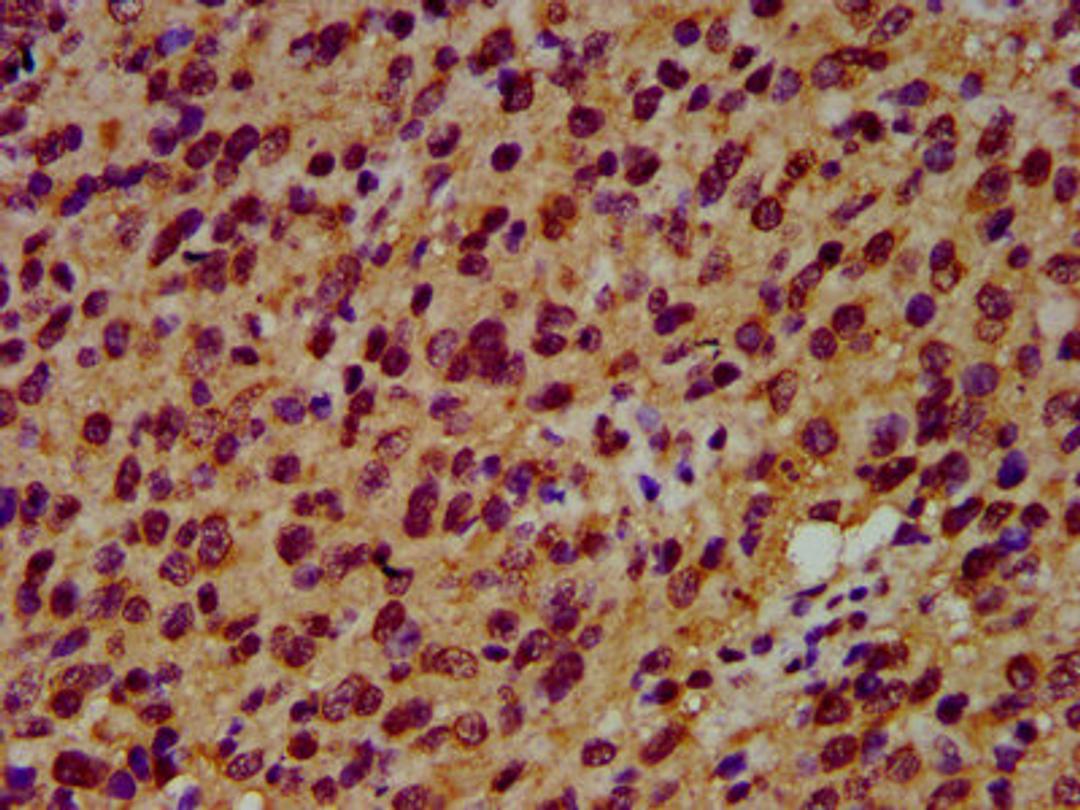

IHC image of CSB-PA021288LA01HU diluted at 1:600 and staining in paraffin-embedded human glioma performed on a Leica BondTM system. After dewaxing and hydration, antigen retrieval was mediated by high pressure in a citrate buffer (pH 6.0). Section was blocked with 10% normal goat serum 30min at RT. Then primary antibody (1% BSA) was incubated at 4°C overnight. The primary is detected by a biotinylated secondary antibody and visualized using an HRP conjugated SP system.